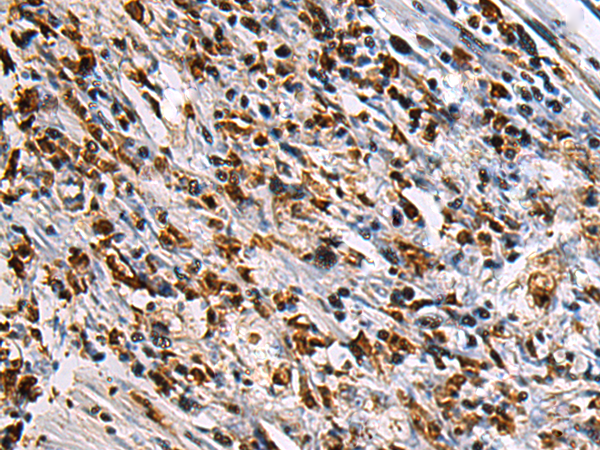

分类: 科研抗体货号: P10442别名: IF; GIF; INF; IFMH; TCN3应用: IHC反应种属: Human, Mouse, Rat